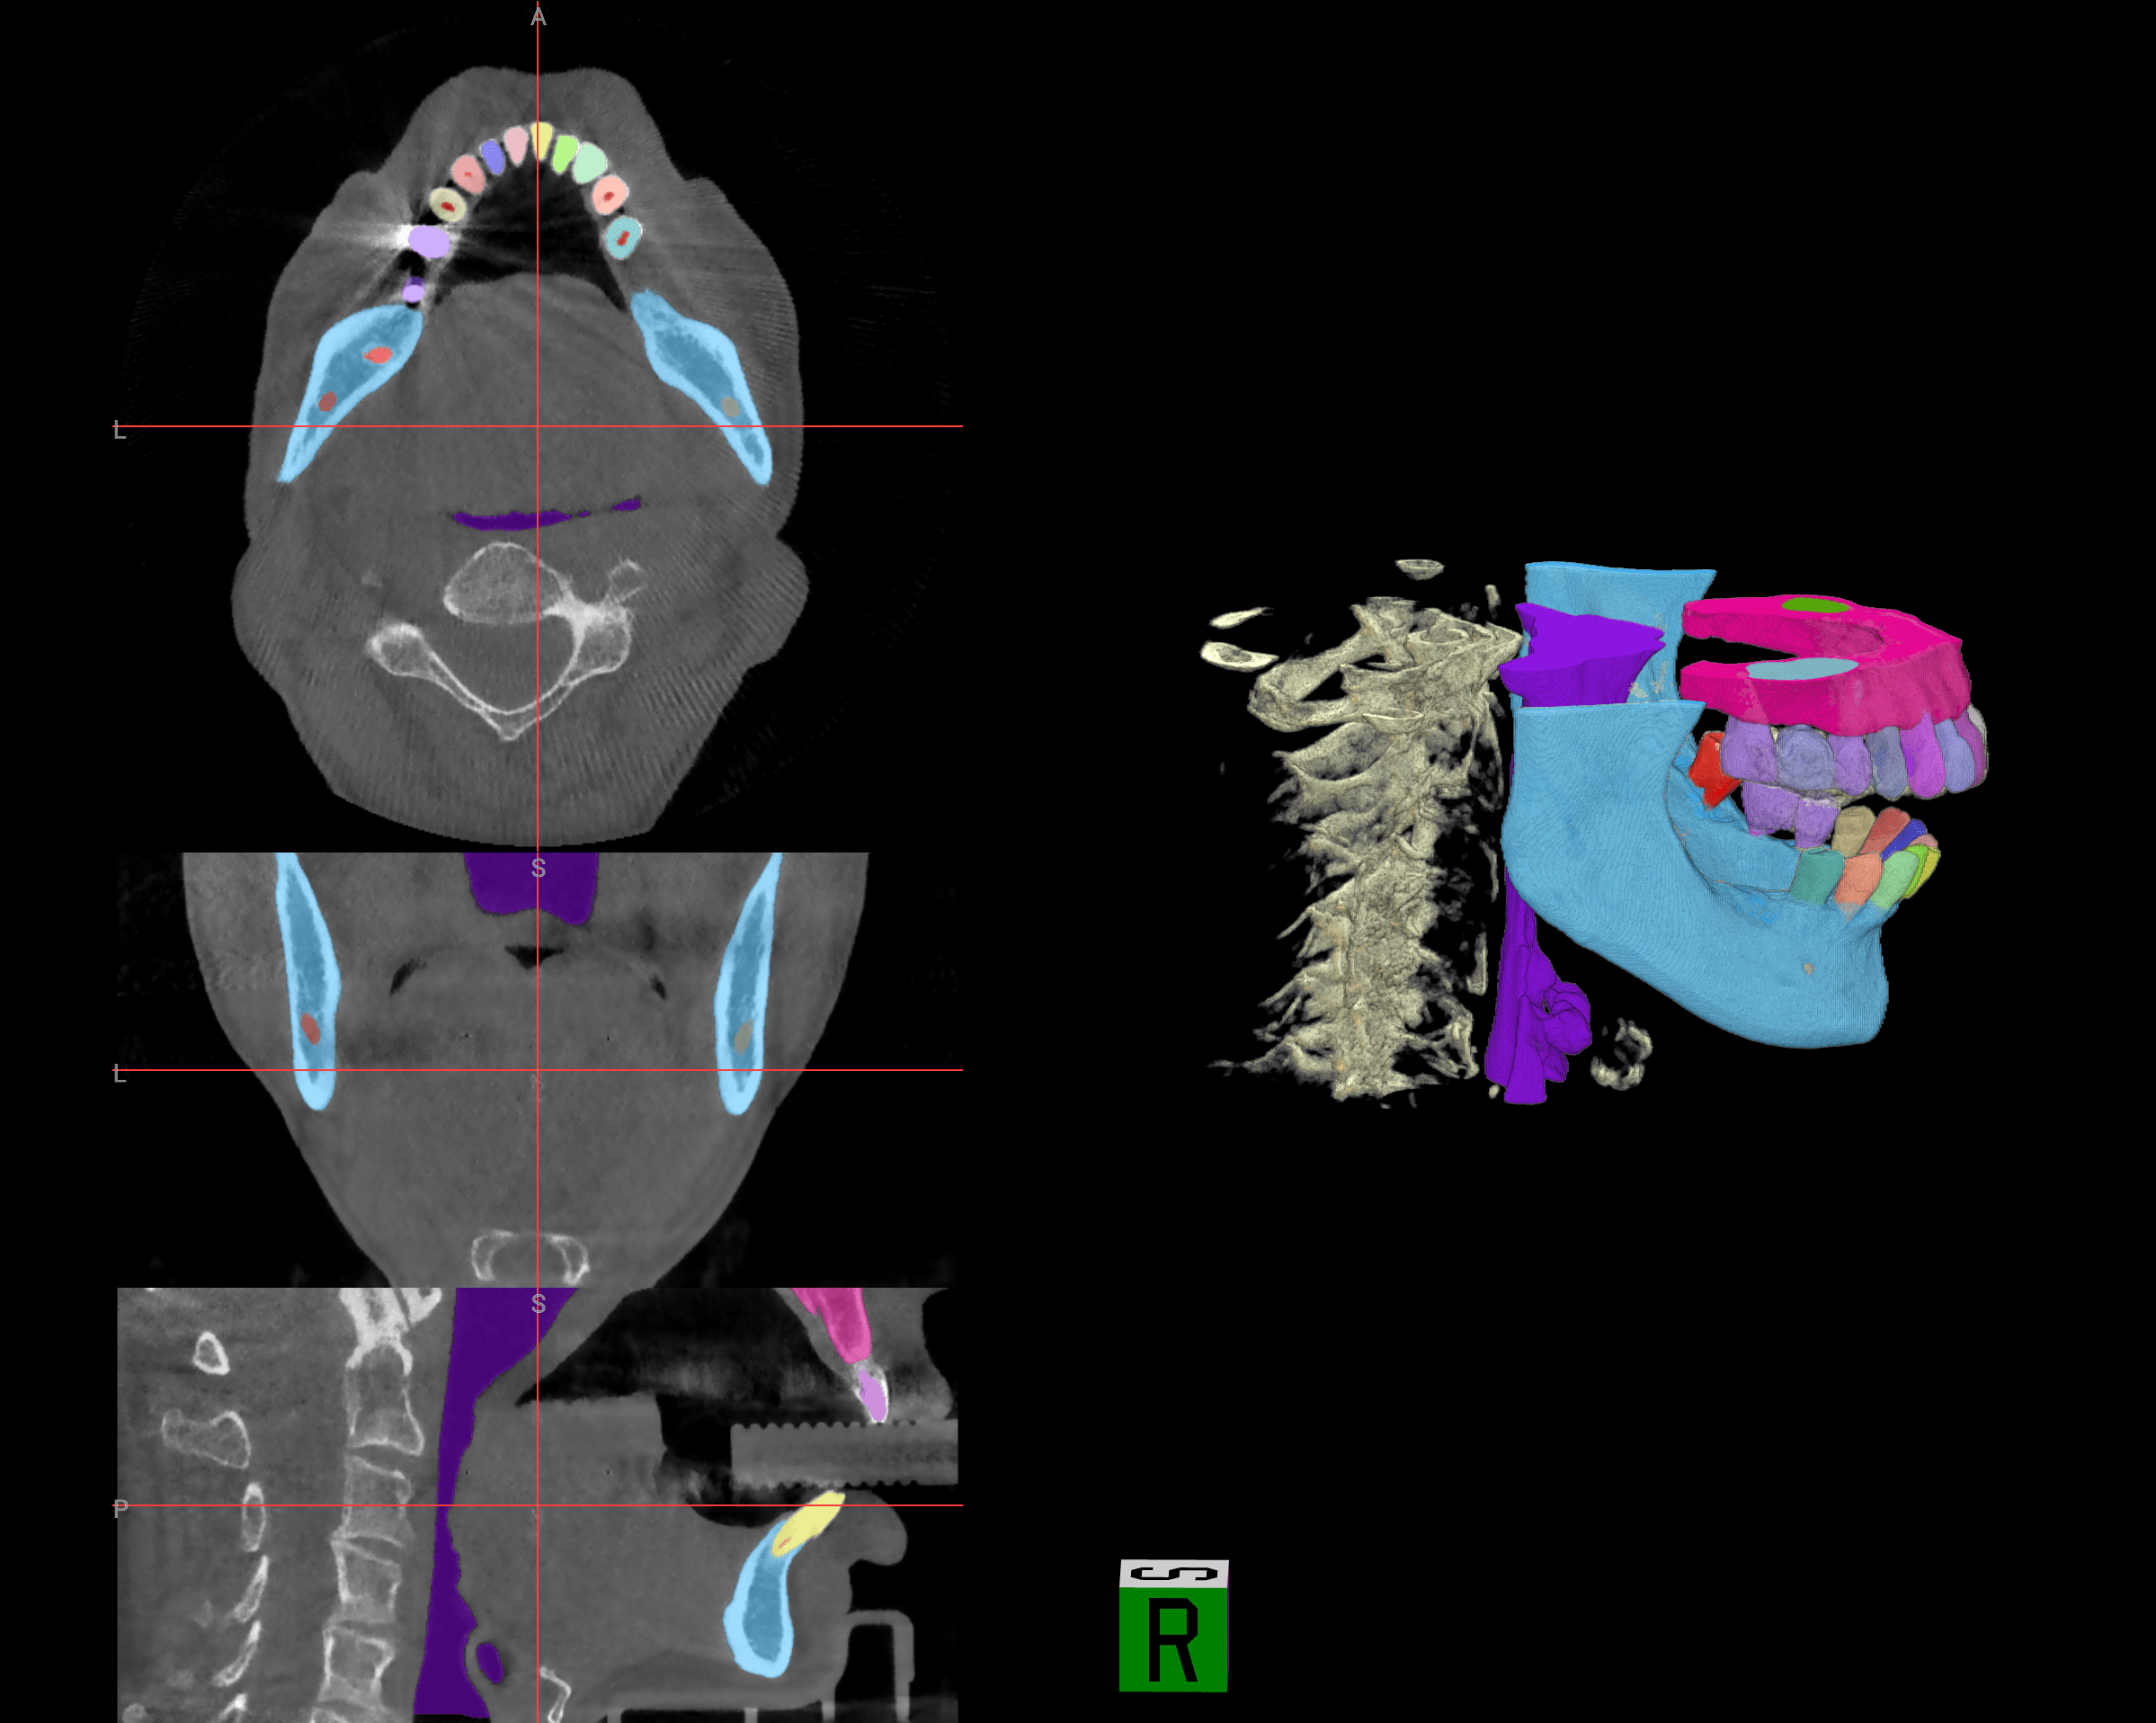

Our multi‑modal AI system includes: CBCT Analyzer & Radious Engine for 3D perception and semantic segmentation; CSI Engine & OLLM (Oral Large Language Model) for cognitive reasoning across 300+ diseases; and an Intelligent Orchestration Layer that delivers findings through conversational interfaces, structured reports, and surgical guide exports.

Advanced conversational interface for clinicians to interact with CBCT scans using natural language. Saves 30-45 minutes per complex case with instant medico-legal reports.